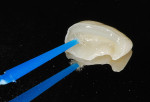

An 18-year-old male patient presented with a visible fracture in the left upper central incisor (tooth No. 9) due to a skateboard accident (Figure 1). The patient did not complain of pain. After the clinical examination, the clinician diagnosed an oblique root-crown fracture of enamel and dentin, with the involvement of the periodontal biologic space but without pulp exposure and mobility (Figure 2). The injury resulted in two dental fragments that were presented by the patient. The fragments were in good condition; they had been properly cleaned and stored in a saline solution for approximately 10 hours, and, in the examination, they adapted to the remaining tooth (Figure 3). The examination, including sensitivity and percussion tests, and the radiographic exams showed normal periapical and periodontal tissues, which gave the appearance of vitality to the damaged tooth, eliminating the need for endodontic treatment (Figure 4 and Figure 5). Thus, since there was no pulp exposure it was proposed to perform only the indirect pulp capping of the pulp-dentin complex, as this was the least invasive approach. The patient was informed about the risks and advantages of the treatment and consented to it.